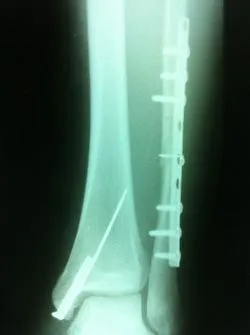

Preop and Postop ORIF Posterior Malleolus Fracture with associated Fibular fracture

Preop and Postop Trimalleolar Fracture with Fixation of Posterior Malleolus Fracture

Preop

Postop